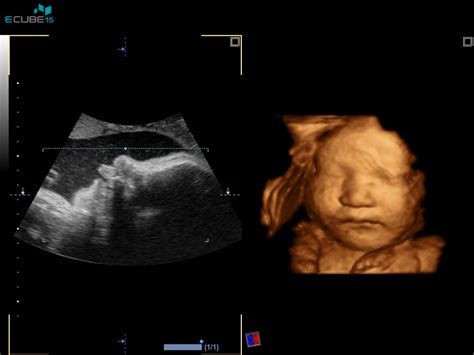

- 3D/4D ultrazvok: Naprednejši ultrazvočni pregled, ki omogoča barvite tridimenzionalne slike ploda in spremljanje njegovih gibov v realnem času. Cene se gibljejo med 60 € in 120 €, pogosto z možnostjo zapisa na USB ali CD.